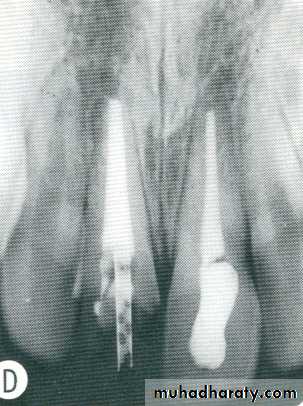

Dental materials. This radiograph shows several metallic and non-metallic dental materials. Since all of the metal restorations are equally radiopaque, their size and shape is observed to determine the type of material. The materials present in this radiograph are: (1) amalgam;(2) porcelain-fused-to-metal crown; (3) post and core; (4) gutta percha; (5) base material; (6) full metal crown, which is the posterior abutment of a three-unit bridge; (7) retention pin; and (8) metal pontic (part of the three-unit bridge).